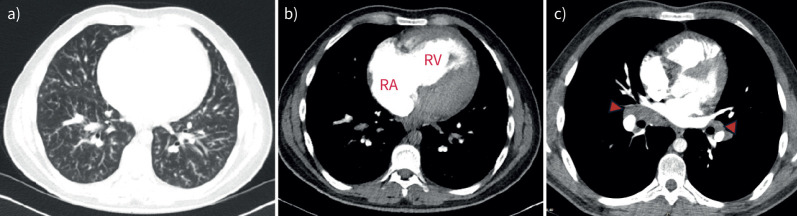

An unprecedented pathology in a 20-year-old with progressive dyspnoea and parenchymal infiltrates.

Sarcoidosis-associated pulmonary hypertension can manifest with a broad range of phenotypes. There may be a role for genetic testing in specific cases of severe disease when the relevance of comorbid sarcoidosis is unclear. https://bit.ly/42kscnz.